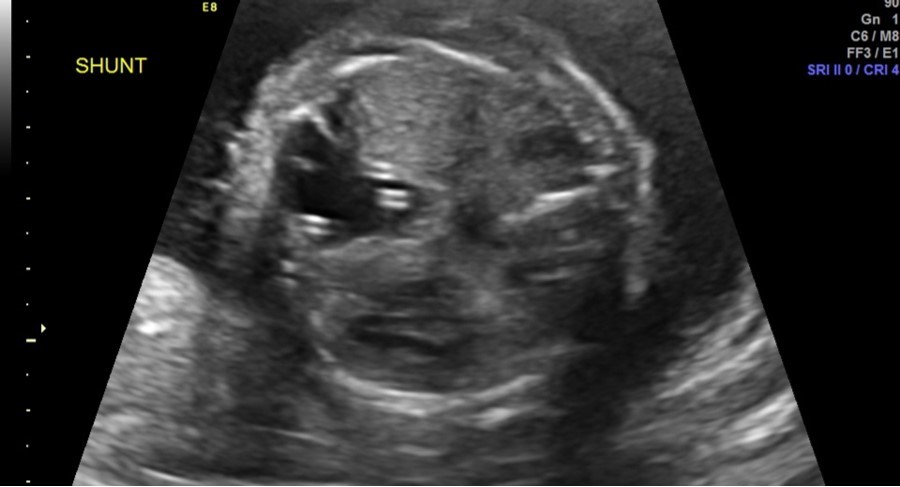

Follow-up parental microarray showed that the 16p11.2 microduplication was maternally inherited. This duplication can be linked with an increased risk of autism or other early onset psychological or neurodevelopmental abnormalities. Fetal MRI was performed at 25 weeks 5 days, noting a large left hemithorax multicystic lesion consistent with CPAM as well as right lung hypoplasia, fetal hydrops, and polyhydramnios. Serial ultrasounds following shunt placement (Figure 2) and CVR (Table 3) noted dislodged shunts on three occasions. With the dislodged shunts, the dominant cyst significantly increased, as did the CVR. On these three occasions (at 24 weeks 3 days, 28 weeks 3 days, and 31 weeks 3 days) repeat thoraco-amniotic shunts, two per procedure, were placed. Immediately after each shunt placement the CVR was notably decreased (Table 3). Amniodrainage was performed at shunt placement when necessary.

Figure 2.Two thoraco-amniotic shunts can be seen in the dominant CPAM cyst

Two thoraco-amniotic shunts can be seen in the dominant CPAM cyst